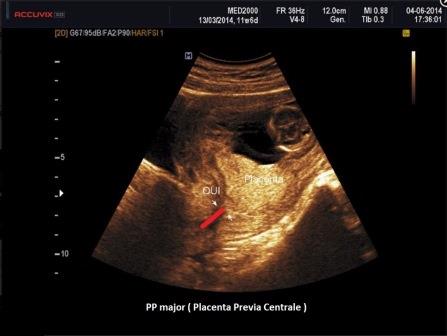

La Placenta previa consiste in un impianto anomalo della placenta: si definisce previa una placenta che nel corso del terzo trimestre si trova localizzata nel segmento inferiore ed è quindi previa nei confronti del feto. La diagnosi definitiva deve essere posta solo dopo la 32a settimana di gestazione preferibilmente con metodica transvaginale.

La Placenta Previa (PP) è classificata ecograficamente a seconda della rilevanza clinica (RCOG 2011 ): se la placenta ricopre interamente l'Orifizio Uterino Interno (OUI) viene considerata PP major (ex PP centrale completa e parziale);

se il bordo placentare si inserisce sul Segmento Uterino Inferiore ma non ricopre l'OUI ed il bordo placentare dista < 2 cm. dall'OUI si parla allora di PP minor (ex PP marginale);

se il bordo placentare si inserisce sul Segmento Uterino Inferiore ma non ricopre l'OUI ed il bordo placentare dista > 2 < 3 cm. dall'OUI si parla allora di PP Laterale o Low-Lying.